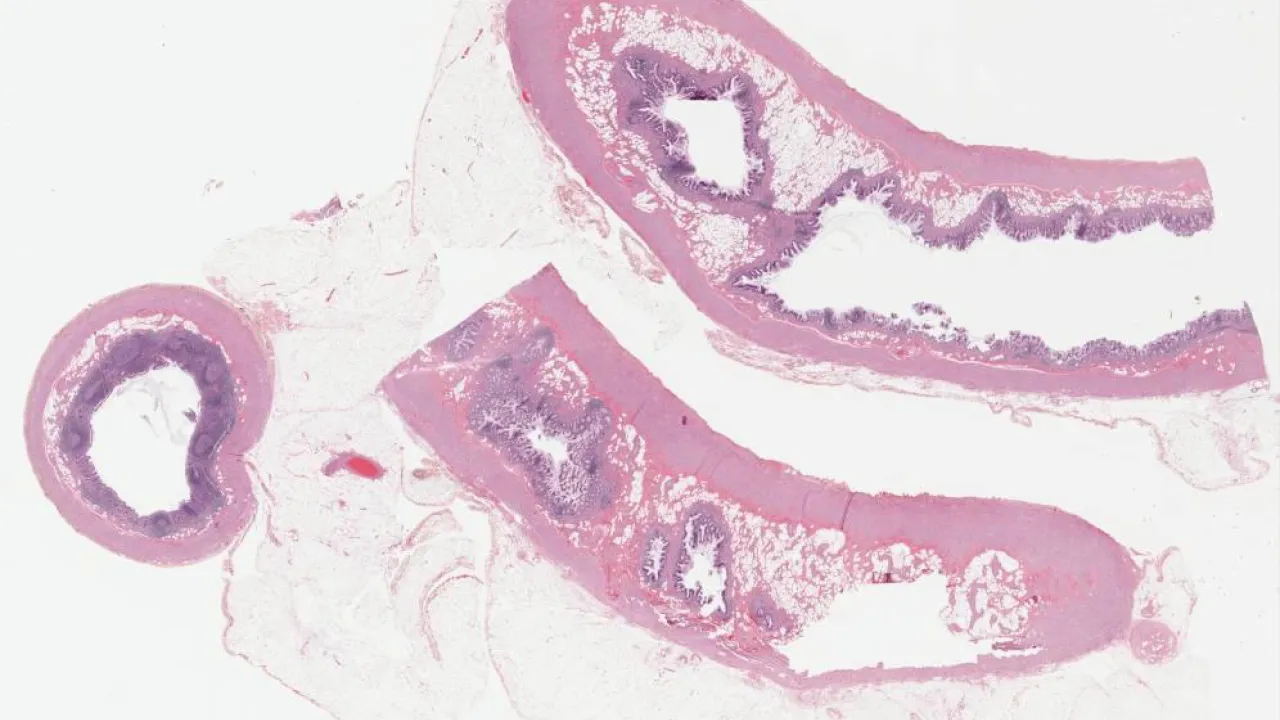

Endocervix, Adenocarcinoma in-situ